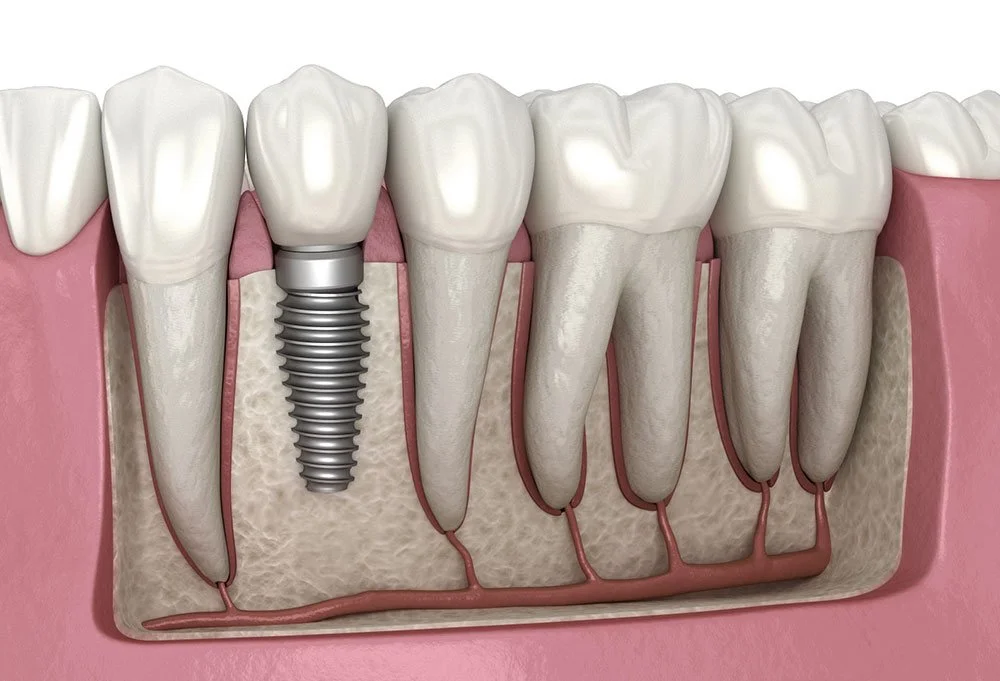

Dental implants are a popular solution for replacing missing teeth. These small titanium posts are surgically placed into the jawbone, serving as strong roots for artificial teeth. Implants look and feel like natural teeth, helping to restore your smile and improve your ability to eat and speak comfortably. Designed to blend seamlessly with your existing teeth, they provide both function and aesthetic appeal. With proper care, dental implants can last a lifetime, making them a durable and effective choice for those seeking to regain their confidence and oral health.